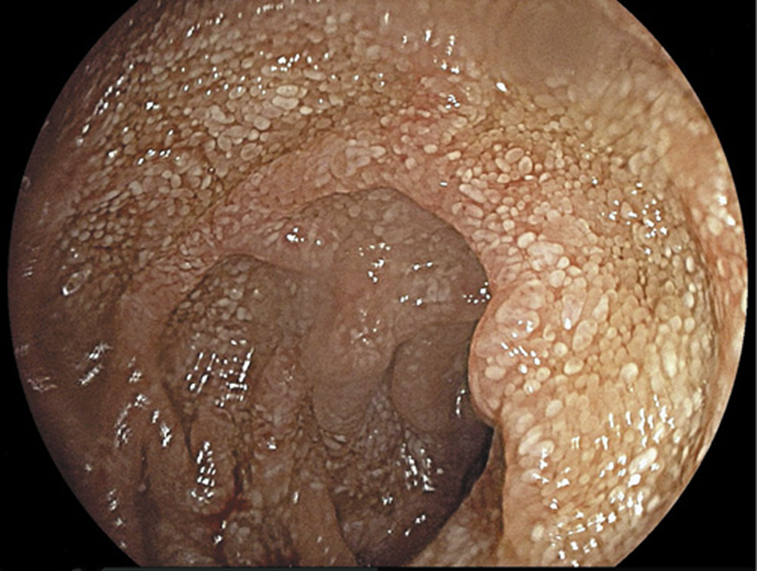

Fig. 2: Upper gastrointestinal endoscopy revealing whitish small plaques diffusely distributed in the intestinal mucosa of the second portion of the duodenum.